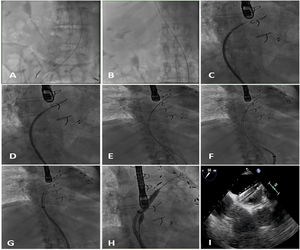

Se acordó implantar un MitraClip (Abbott Vascular, Estados Unidos) (figura 1) a una mujer de 79 años. Se obtuvo el consentimiento informado pertinente. Los intentos de punción transeptal (PTS), mediante una vaina Mullins y una aguja Brockenborough curvada manualmente en diversos ángulos, no dieron resultado debido a una pronunciada tortuosidad venosa. Los intentos de enderezar la vena cava inferior (VCI) con una vaina de calibre 14 Fr fueron infructuosos. Se utilizó entonces un catéter dirigible Agilis de curva media (St. Jude Medical, Estados Unidos) para alcanzar la fosa oval. Se realizó una PTS aplicando una breve descarga de energía de radiofrecuencia (∼ 60W) a una guía Confianza de 0,014” (Asahi Intecc, Estados Unidos). A continuación se introdujo la vaina Agilis en la aurícula izquierda (AI) y se colocaron 2 guías, Amplatz Superstiff y Extrastiff (Boston Scientific, Estados Unidos), en la vena pulmonar superior izquierda. Se retiró la vaina de 14 Fr y, tras dilatar el acceso venoso (18 Fr), se introdujo el catéter guía (CG) dirigible de 24 Fr sobre la guía Superstiff. Sin embargo, seguía siendo imposible atravesar el tabique interauricular (TIA) con el CG debido al poco apoyo y posibilidad de empuje en la VCI tortuosa. Se mantuvo el CG en la aurícula derecha y se introdujo una vaina de calibre 7 Fr sobre la otra guía (Amplatz Extrastiff). A continuación, se realizó una septostomía con balón de angioplastia transluminal percutánea de 10 × 40mm y, tras deshinchar el balón, se introdujo el CG de 24 Fr en la AI (figura 2). Por último, se colocó un MitraClip para tratar un prolapso A2-P2 (figura 3).

En una VCI tortuosa, el acceso al TIA puede facilitarse con una PTS asistida por electrocauterización, una septostomía con balón y la técnica de guía acompañante para introducir la vaina al tiempo que se deshincha el balón y se tracciona de él.